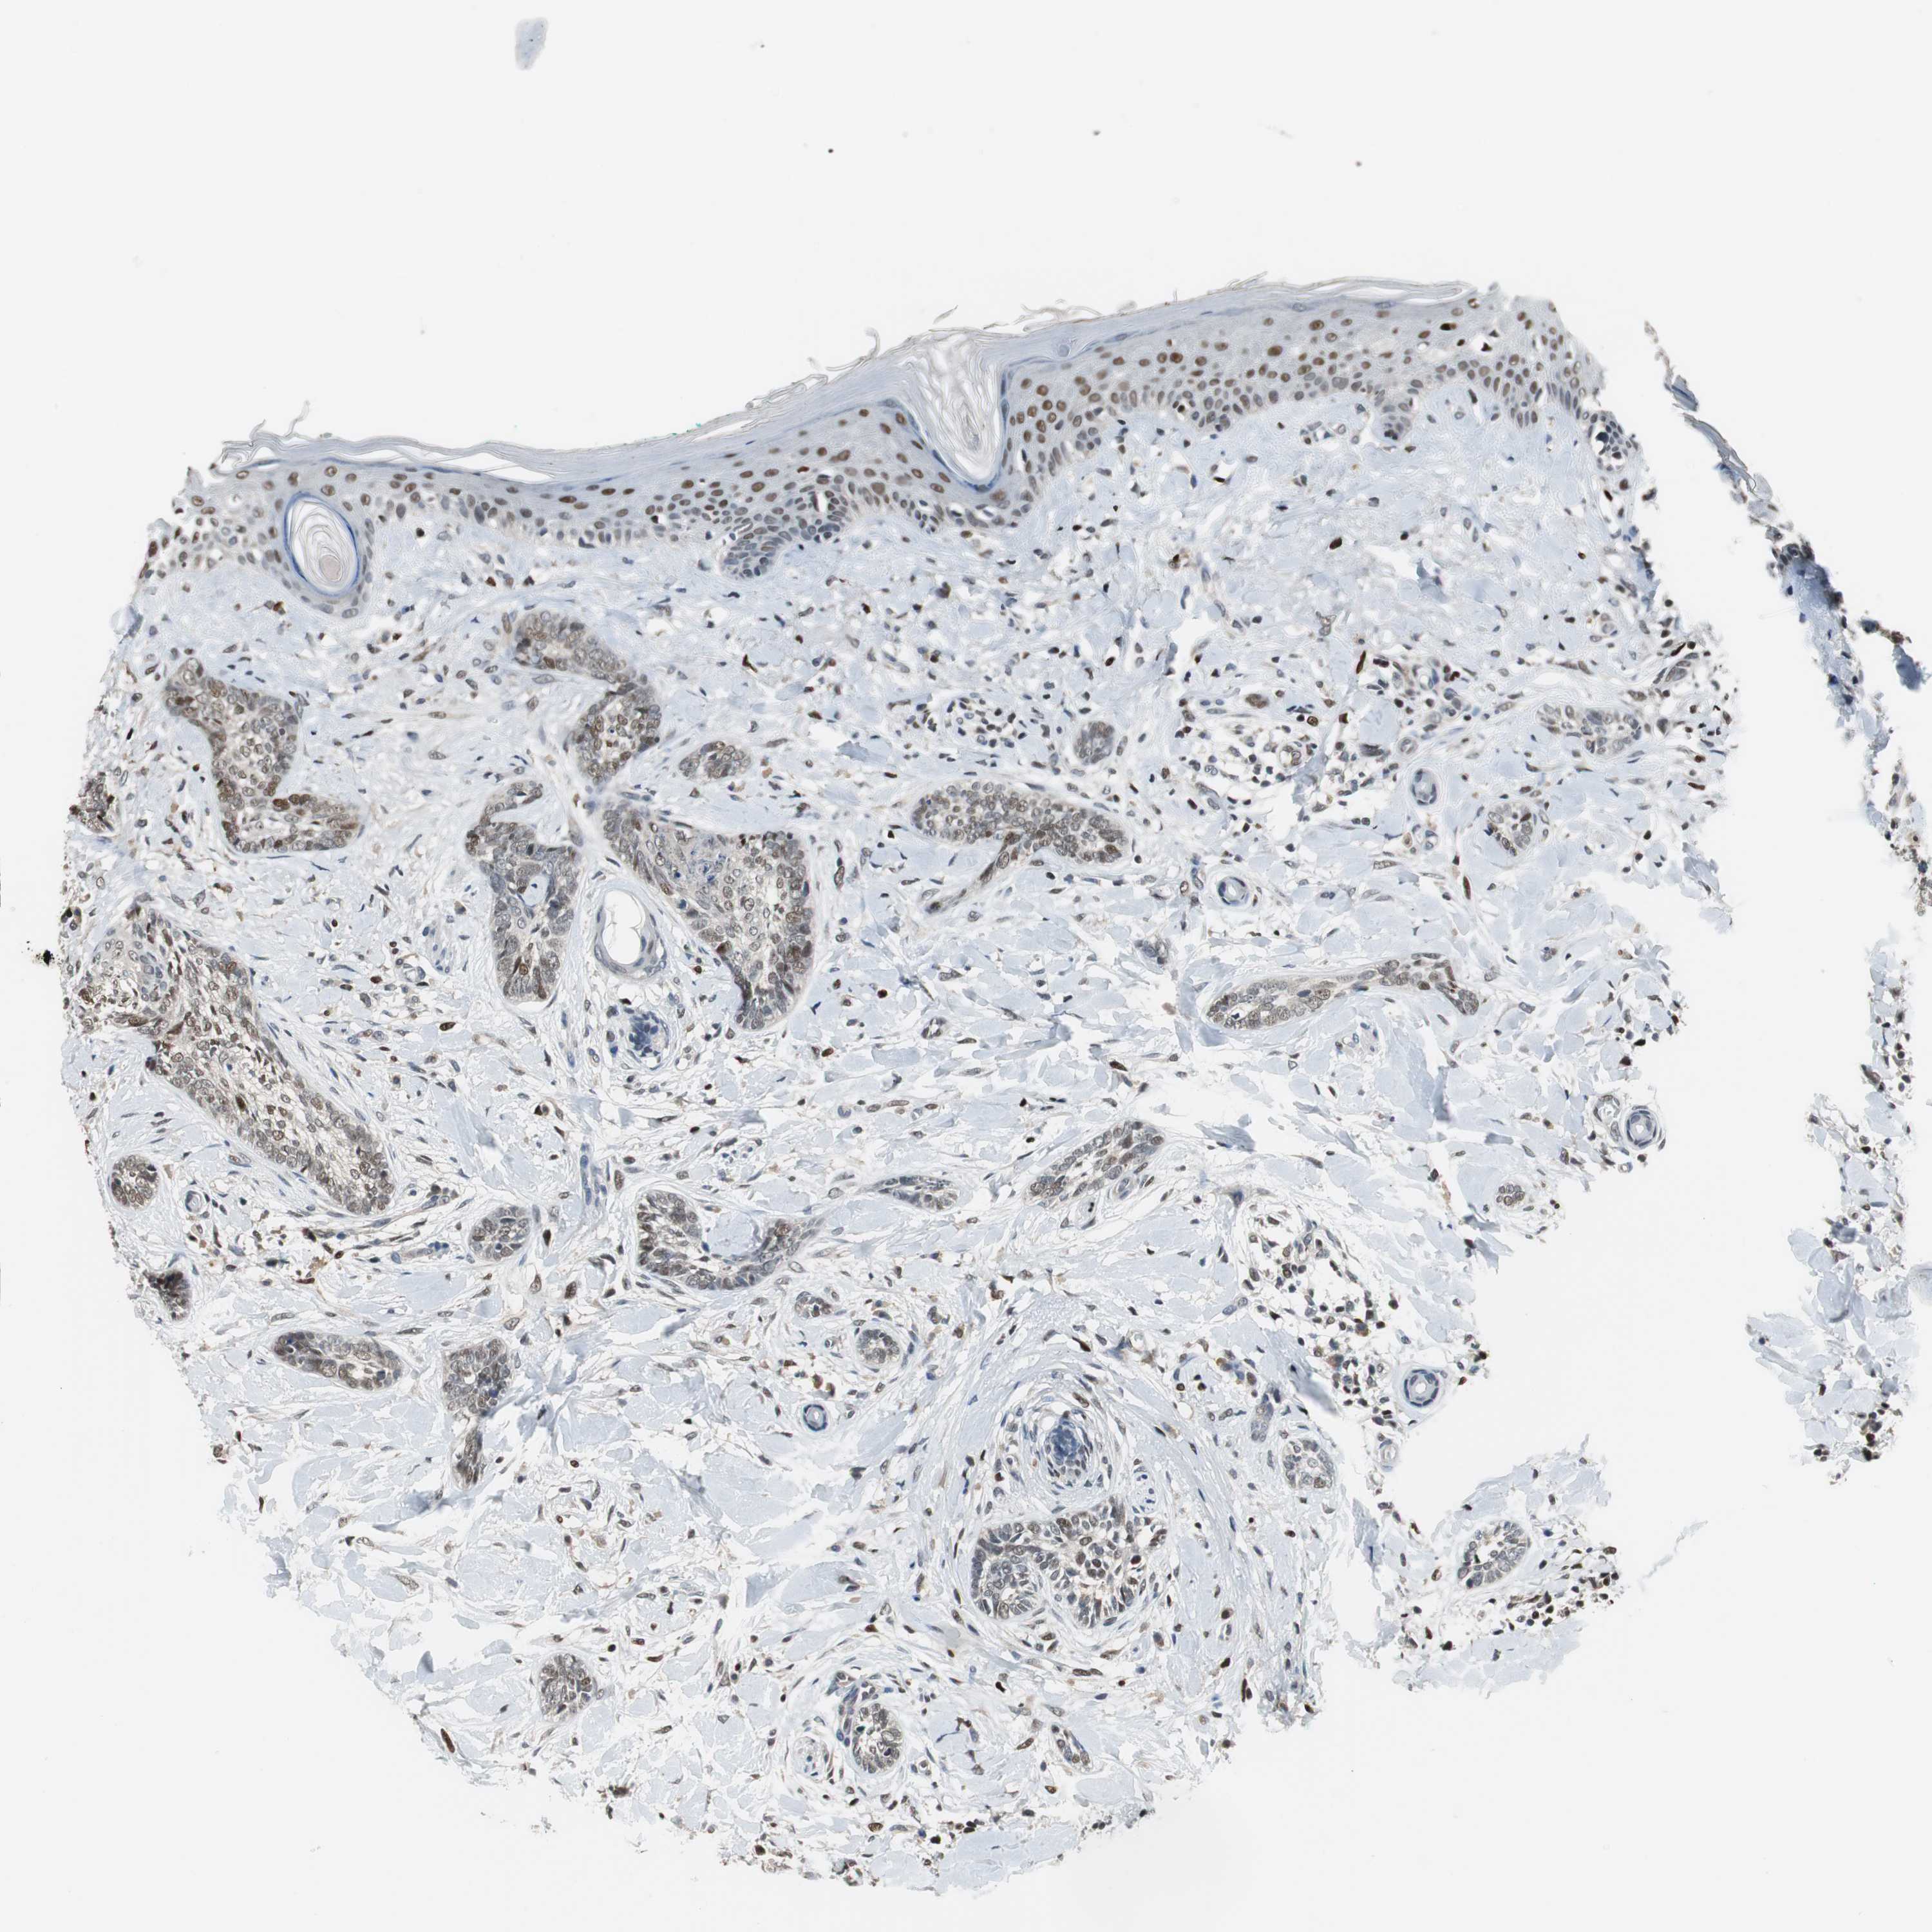

SKIN CANCER - Protein expressioni

A mouse-over function shows sample information and annotation data. Click on an image to view it in a full screen mode. Samples can be filtered based on level of antibody staining by selecting one or several of the following categories: high, medium, low and not detected. The assay and annotation is described here.

Antibody stainingi

Antibody staining in the annotated cell types in the current human tissue is reported as not detected, low, medium, or high, based on conventional immunohistochemistry profiling in selected tissues. This score is based on the combination of the staining intensity and fraction of stained cells.

Each image is clickable and will lead to virtual microscopy that enables deeper exploration of all samples and also displays staining intensity scores, fraction scores and subcellular localization as well as patient and tissue information for each sample.

Antibody HPA005653

Staining

High

Medium

Low

Not detected

Intensity

Strong

Moderate

Weak

Negative

Quantity

>75%

75%-25%

<25%

None

Location

Nuclear

Cytoplasmic/membranous

Cytoplasmic/membranous,nuclear

Squamous cell carcinoma, NOS

Basal cell carcinoma